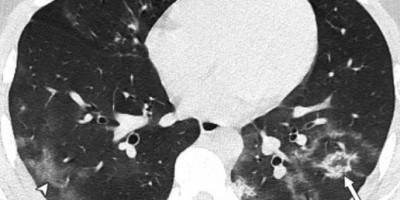

Korona uništava pluća i mladim i zdravim ljudima, a još jedan dokaz za to stiže nam iz Grčke.

Grčki epidemiolog i član tamošnjeg Kriznog štaba dr Gikas Majorkinis objavio je na svom Fejsbuk profilu snimke pluća maloletnih pacijenata koji su oboleli od kovida-19, ističući da jedna slika govori više od 1.000 reči.

- Ovo su snimci pluća ljudi koji su imali kovid, a koji su mlađi od 18 godina (15, 14 i 8 godina). Nijedan od njih nije imao bilo kakve druge bolesti niti imunosupresiju. Nije im bio potreban kiseonik, intubacija niti intenzivna nega. Ovo su jednostavne i česte posledice korone - napisao je on i dodao.

- Ova pluća imaju veoma impresivno oštećenje i nije poznato šta ona mogu vremenom da uzrokuju.

- Imam jednostavno pitanje za sve: da li želite da izložite pluća ovakvom riziku i vidite da li ona mogu da podnesu to? A ako izdrže, kao što verovatno hoće kada je reč o mladim ljudima, da li zaita želite da vidite koliko godina ili snage ste izgubili?

Na kraju posta, doktor je apelovao na sve da se vakcinišu, jer će tako sačuvati svoja pluća.